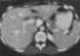

Calcified lymph nodes at porta hepatis